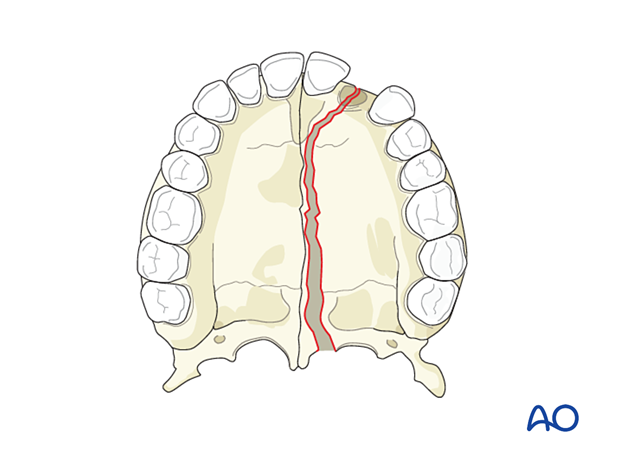

A simple palatoalveolar fracture divides the palate into two palatoalveolar fragments.

Simple (noncomminuted) palatal fractures are commonly associated with Le Fort I fractures but can be seen with other midface complex fractures. They are almost always longitudinal, and in adults, parallel to the center. In children, where the midline palatal suture is open, they divide at the center. Rarely, palatal fractures are transverse or oblique.